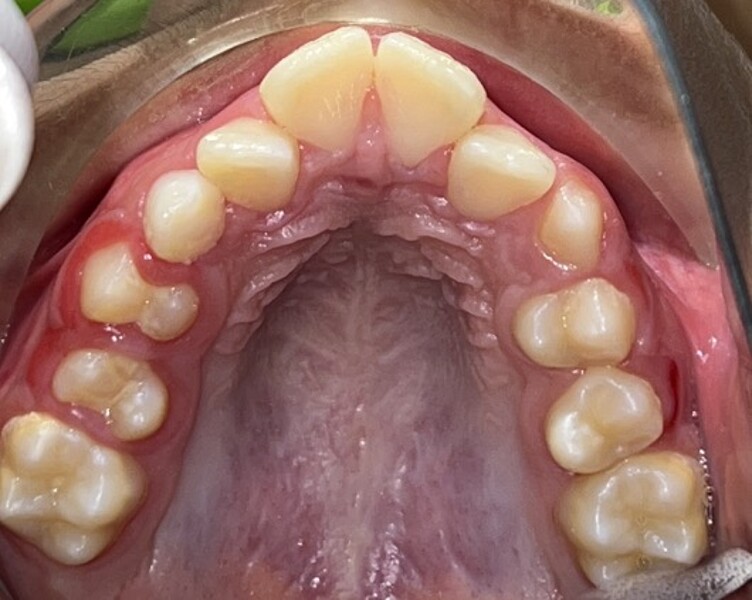

Figs. 2a–e: Pretreatment intra-oral photographs.

Clinical and radiographic evaluation revealed (Figs. 1–3):

a bilateral full-cusp Class II molar relationship;

an increased overjet of 11.7 mm;

a traumatic overbite of 7.2 mm; and

a narrow, collapsed V-shaped maxillary arch with a 2.0 mm midline deviation to the right.

Cephalometric analysis confirmed a Class II skeletal pattern primarily caused by mandibular retrusion (ANB = 5°; SNB = 69°) and showed reduced mandibular length (94 mm versus a norm of approximately 110 mm; Fig. 4; Table 1). The vertical pattern was normo-divergent (SN/GoGn = 34°). Dentoalveolar analysis showed severe maxillary incisor proclination, pronounced crowding in both arches and an accentuated curve of Spee. Soft tissue analysis showed lower lip entrapment associated with the increased overjet, contributing to an unfavourable facial profile.